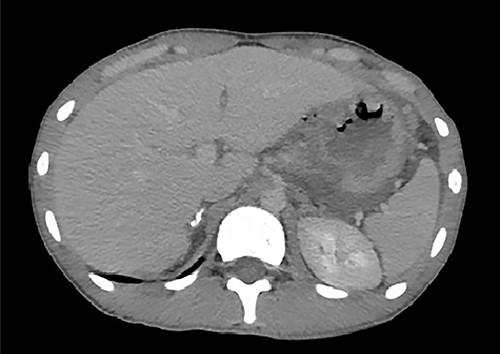

A 18-year-old male without relevant past medical history was admitted to the emergency department 2 hours after a motor vehicular collision. At admission, we evaluated according to the Advanced Trauma Life Support algorithm. The airway was permeable and the respiratory physical examination was normal. The patient presented tachycardia and reported severe generalized abdominal pain. Abdominal inspection revealed an abrasion zone measuring 5 × 6 cm in the left hypochondrium without active bleeding. On palpation, the abdomen was tender and guarded. He was conscious, with a Glasgow coma score of 15/15. Laboratory tests revealed hemoglobin of 14 g%. Chest X-rays were normal. Computed tomography (CT) of the abdomen revealed pneumoperitoneum with a moderate amount of intraperitoneal free fluid and discontinuity of the stomach wall, suggesting full thickness perforation at this level (Fig. 1).

An axial image from the abdominal CT scan demonstrates discontinuity of the stomach wall and a connection with the free air, suggesting perforation at this level.